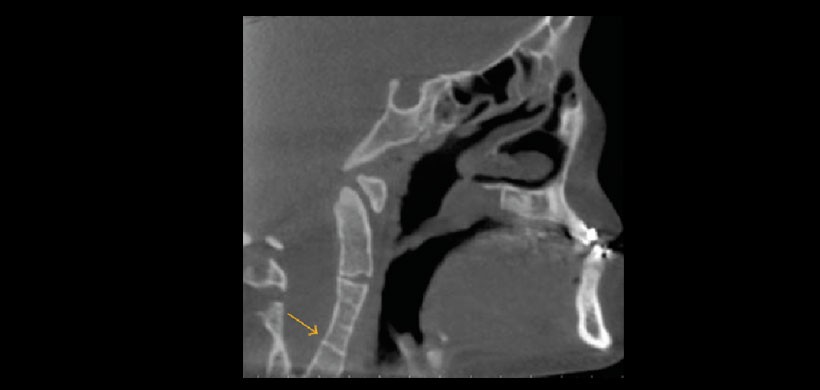

Fig 5. Tomografía volumétrica, vista coronal. Muestra cambios degenerativos (osteoartritis) a nivel de C3 y C4 con formación de osteofito.

Fig 6. Tomografía volumétrica, vista saital. Muestra fusión de vértebras cervicales (C3 y C4).